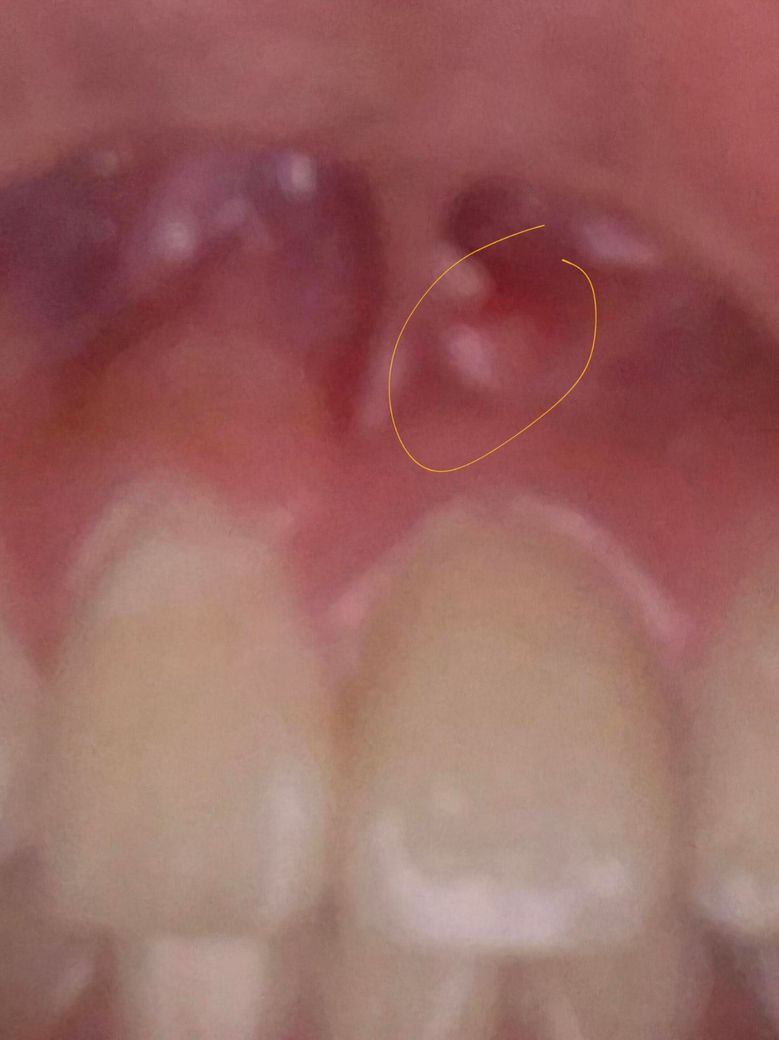

잇몸에 이물감이 느껴져서 다녀왔는데 이게 뭘까요?

한 2주 전에 잇몸 뭐가나서 치료하고

저번주 수요일에 한번 더 확인도 했었는데 이번에

작은 이물감이 느껴져서 치과를 다녀왔단 말이죠

근데 아무것도 아니라고 이상 없다고 하셨는데

그럼 뭔지 궁금합니다. 알려주세요.

• 1번 째 사진

사진으로 봤을 경우 근단주위 치주염일 가능성이 있습니다. 신경관에 감염이 되면 염증이 치조골 밖으로 나오게 되면서 생기는 증상입니다.

정확한 확인을 위해서는 방사선 사진이 필요하기 때문에 자세한 확인을 위해서 치과에서 진료를 받아보는 것을 권유드립니다.

잇몸에 무엇이 난 것이 맞다면 염증일 수도 있지만 치과에서 문제 없다했으면 침샘 일수도 있습니다.

사진에 보이는 부분에서 계속 여드름 처럼 염증이 생기면 치아 뿌리끝에 염증이 잇어서 그럴수도 있습니다.

사진 초점이 맞지 않아 정확히 보이진 않으나 gingiva epulis 의 가능성이 있어보입니다 국소적으로 잇몸을 자극하는 자극원이 무엇인지 찾아봐야할 것 같습니다.